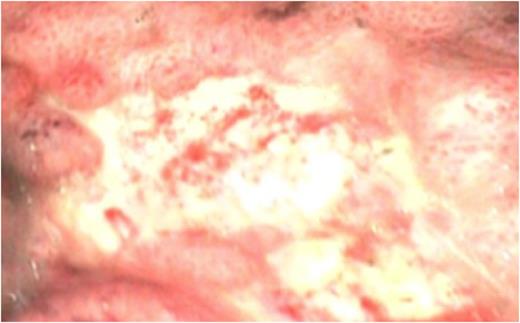

Multiple punctate mucosal lesions raised the suspicion of emerging gastric ischaemia secondary to band migration (fig.2), and the patient proceeded to an urgent laparoscopy.